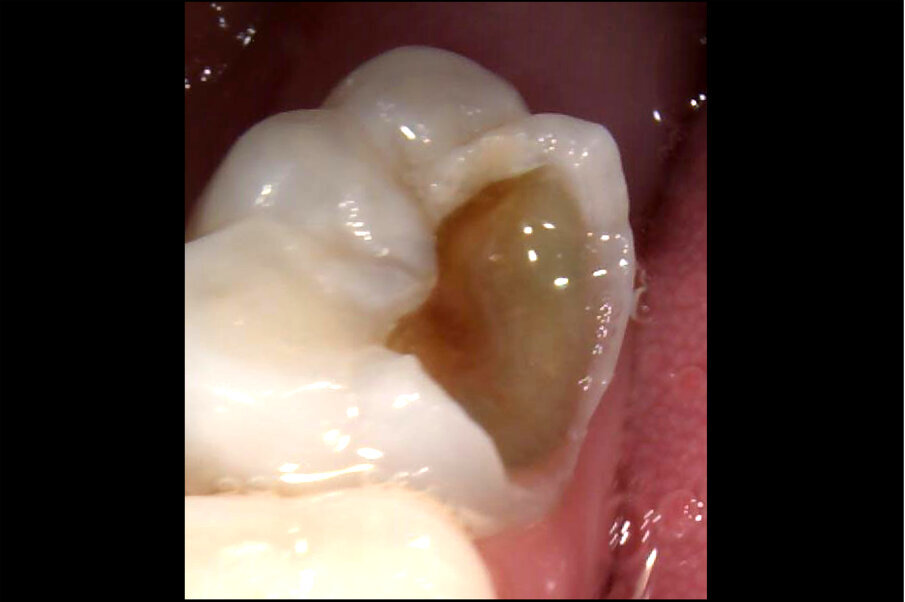

Afbeelding 3. Casus 2: 29-09-17. Eerste bezoek. Actieve cariës-instructies en ZDF aangebracht.

Afbeelding 4. Casus 2: 09-02-18. Tweede bezoek. Na 4 maanden klachtenvrij.

Afbeelding 5. Casus 2: 25-05-18. De caviteit in 74 blijkt niet goed reinigbaar, daarom Fuji Triage geplaatst.

Afbeelding 6. Casus 2: 18-10-18. Fuji Triage ‘noodvulling’ voldoet na 5 maanden.